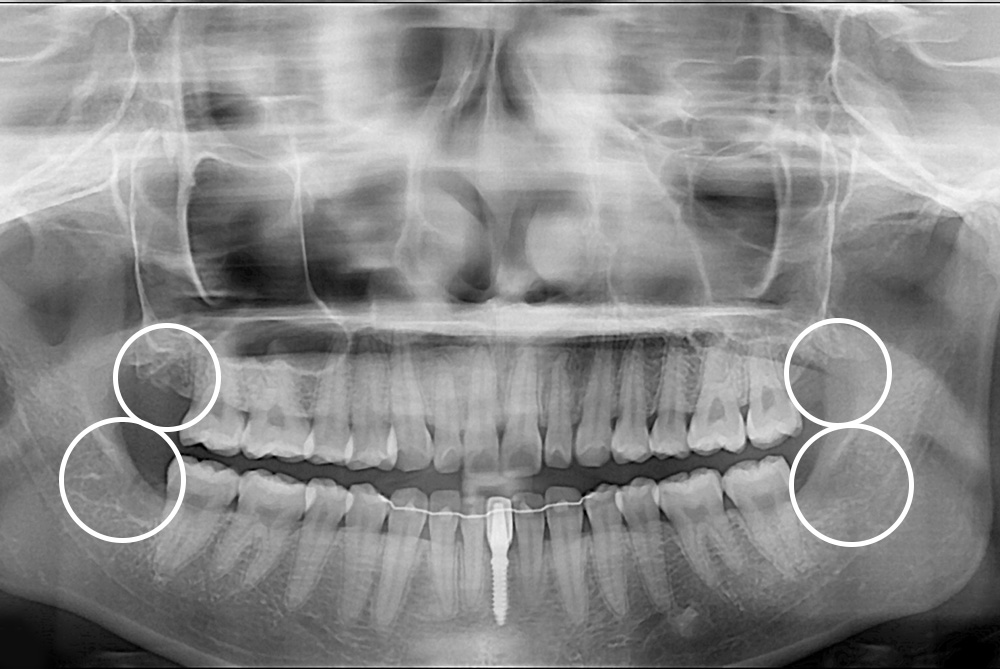

[사랑니] 매복 사랑니 발치

치료후 : 2019-04-24

세종치과는 구강악안면외과학 박사이신 원장님이 발치하는 치과입니다.